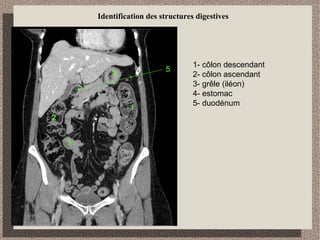

Identification des structures digestives

1- côlon descendant

2- côlon ascendant

3- grêle (iléon)

4- estomac

5- duodénum